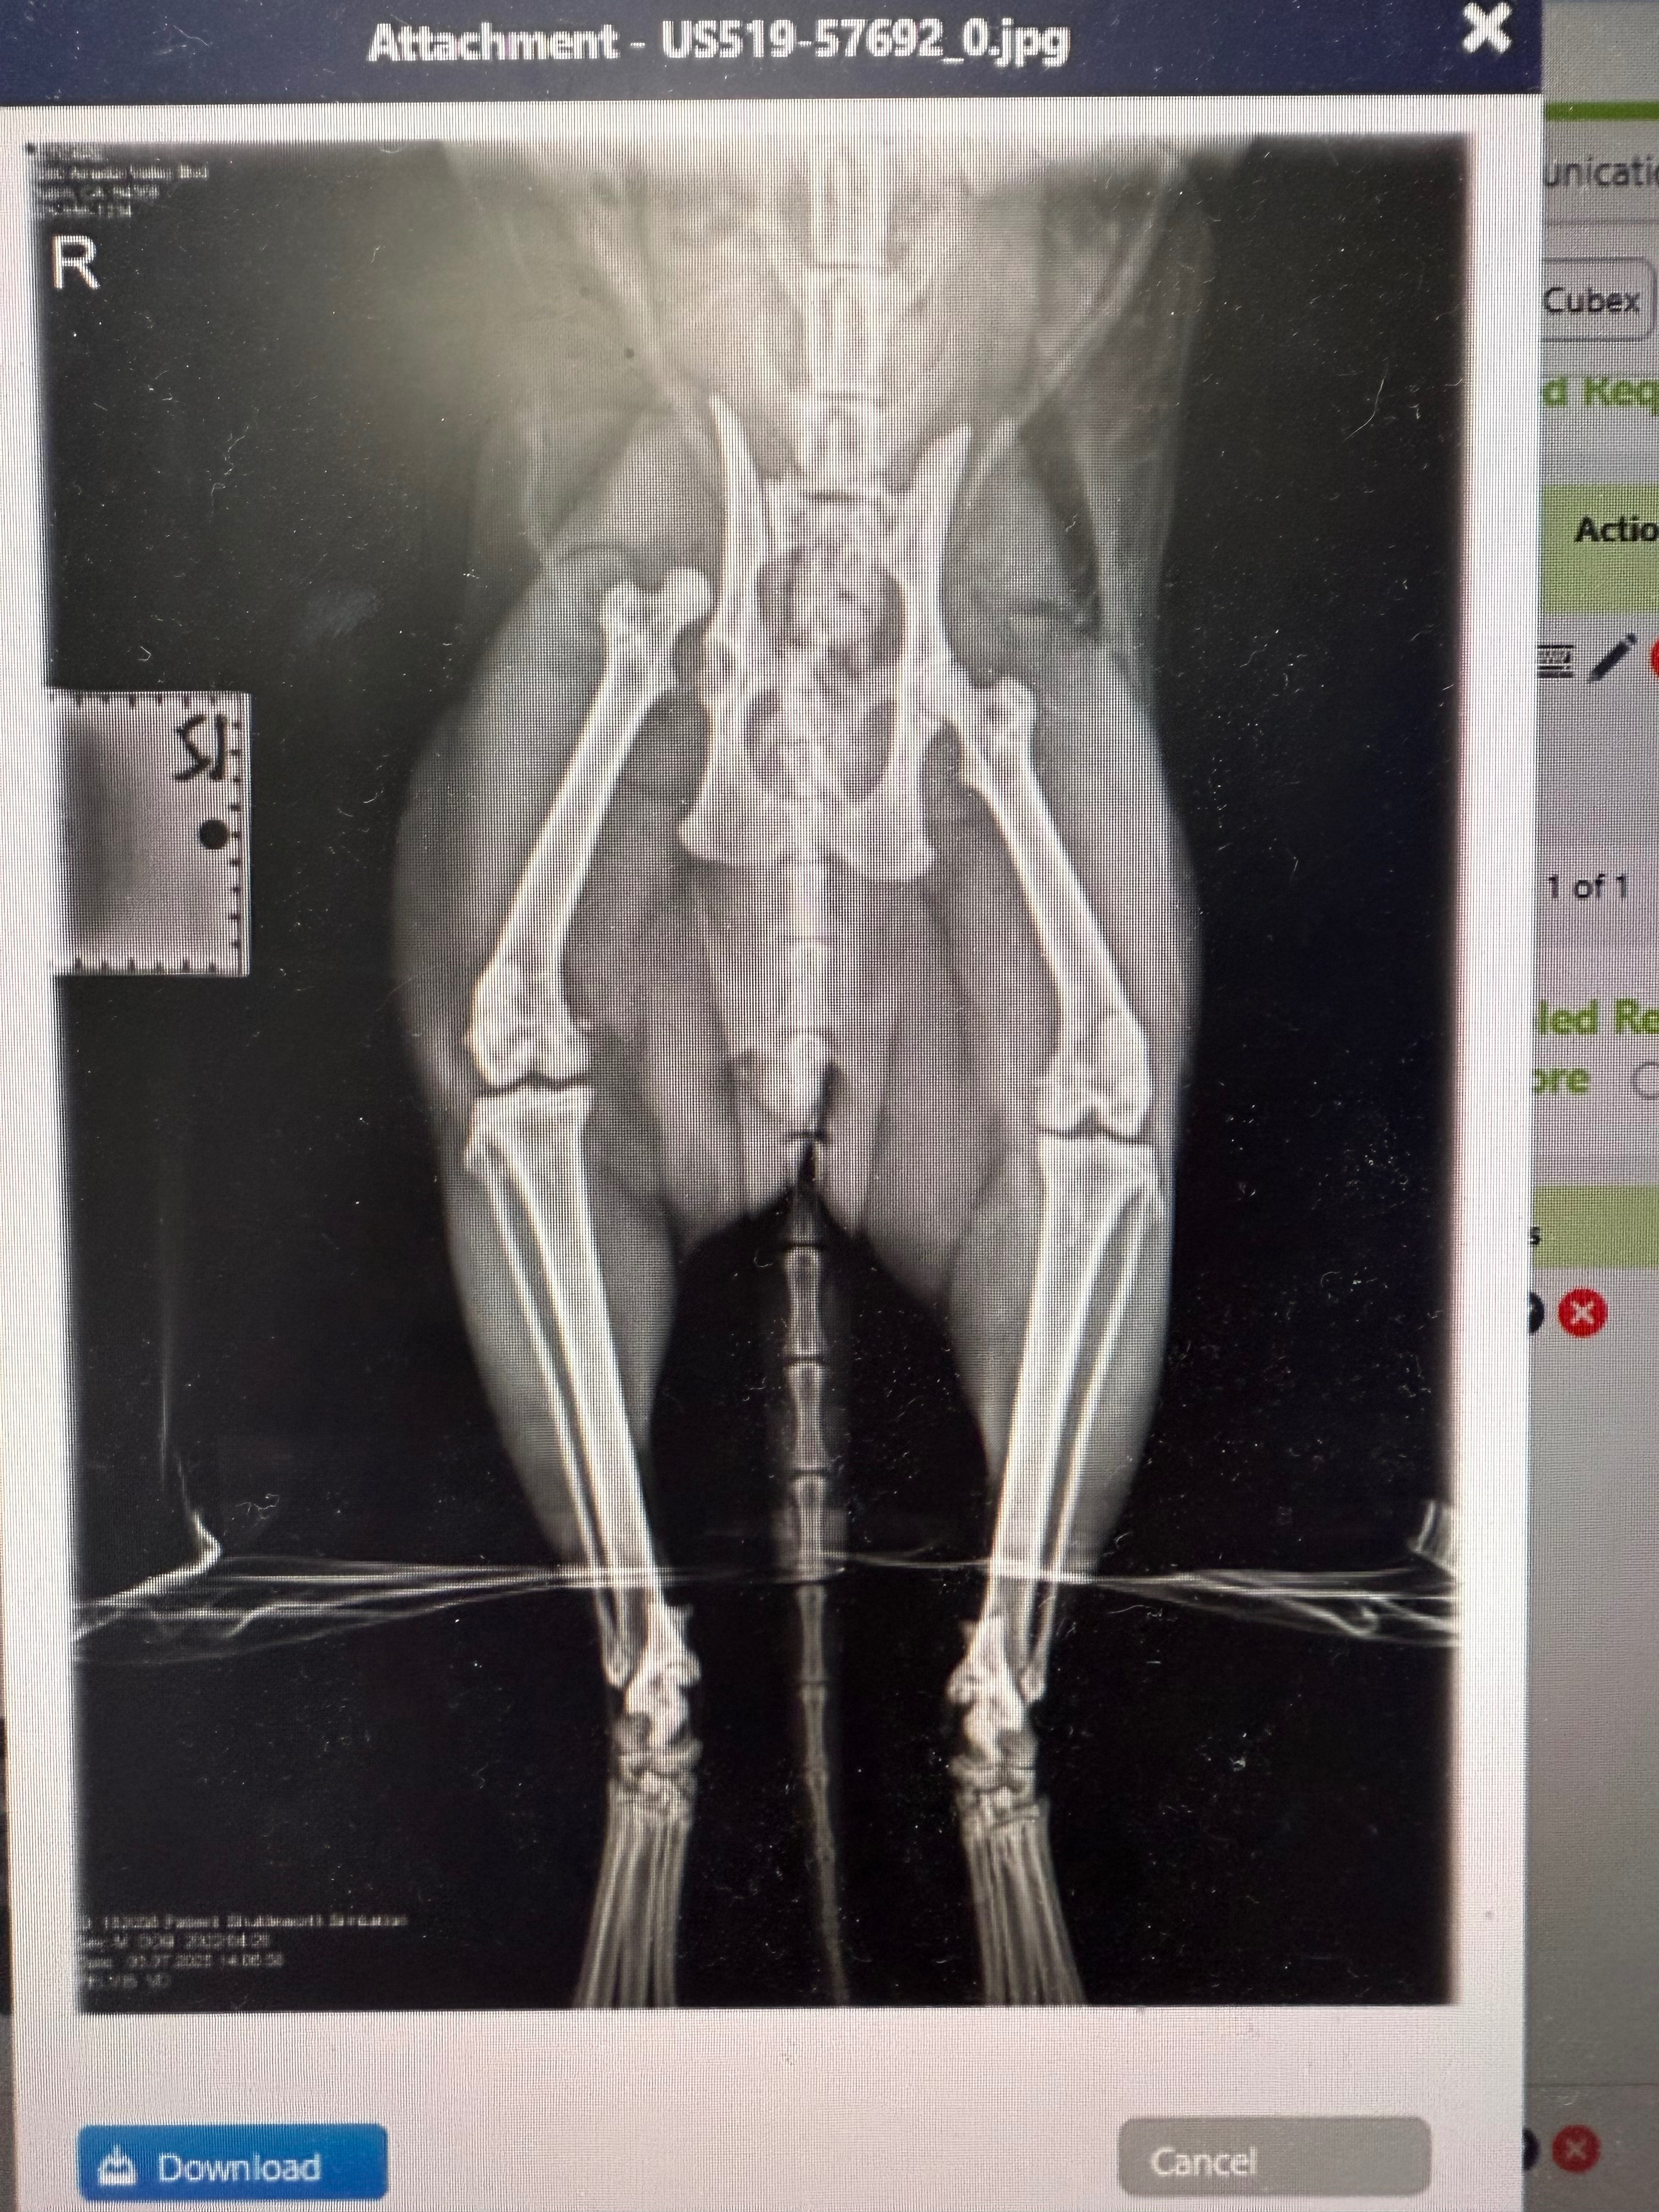

our poor family cat Simbatron aka Simba was hit by a speeding car in front of our house and popped out his hip. The car didn’t stop to make sure he was okay, but luckily I was outside and heard the commotion and saw Simba running awake and dragging his hind legs. The surgeon he saw tried to popped his hip back into place but with how bad the damage was, it didn’t stay. Now he had to have surgery to remove the femoral head that connects the hip and femur together. This is a pricey surgery but Simba is the favorite pet in our family and we want to try to save his leg. Any help is greatly appreciated to go towards simbas surgery. The kids want their Simba back!